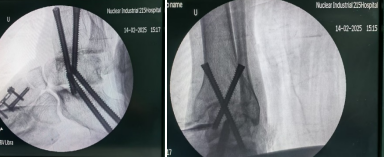

术中情况